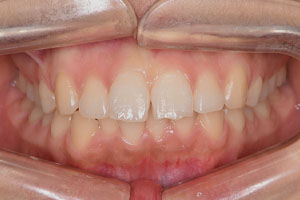

치료증례 전후사진

Before & After